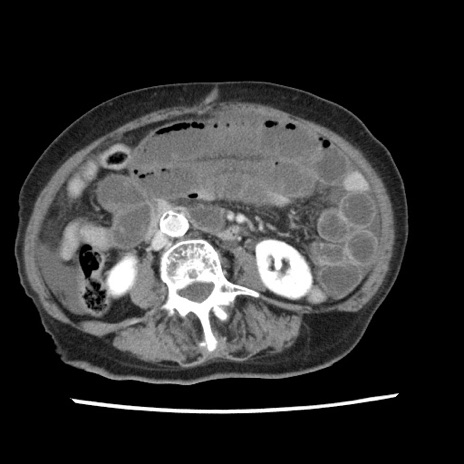

矢状断像

【症例】80歳代女性

【主訴】腹痛

【現病歴】8時間前から腹痛あり来院。

【既往歴】糖尿病、脂質異常症、子宮体癌にて子宮全摘術

【身体所見】意識清明・会話良好だが腹痛で苦悶様、全腹部にわたって反跳痛と圧痛あり

【データ】WBC 13600、CRP 0.14、LDH 224、CK 90